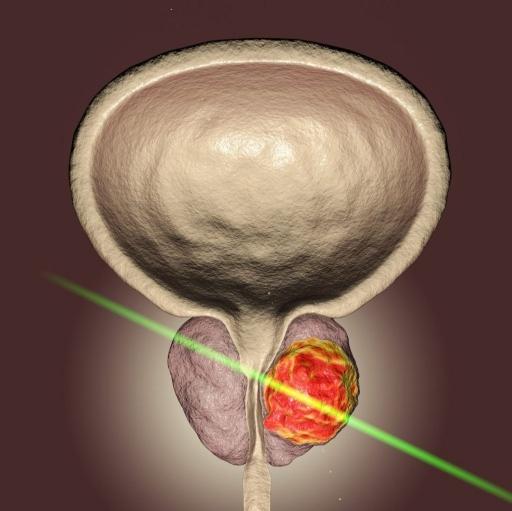

Cáncer de próstata

Crecimiento prostático • Verrugas genitales • Disfunción eréctil y vasectomía

• Cirugía laparoscópica y láser • Cáncer de riñón, próstata, testicular y de vejiga

Cirugía láser de próstata y piedra, Laparoscopía urológica,

Riñones, Cáncer urogenital, Cirugía percutanea de cálculos, Endourología.

Láser para incontinencia urinaria sin cirugía, Termoablación de tumores.